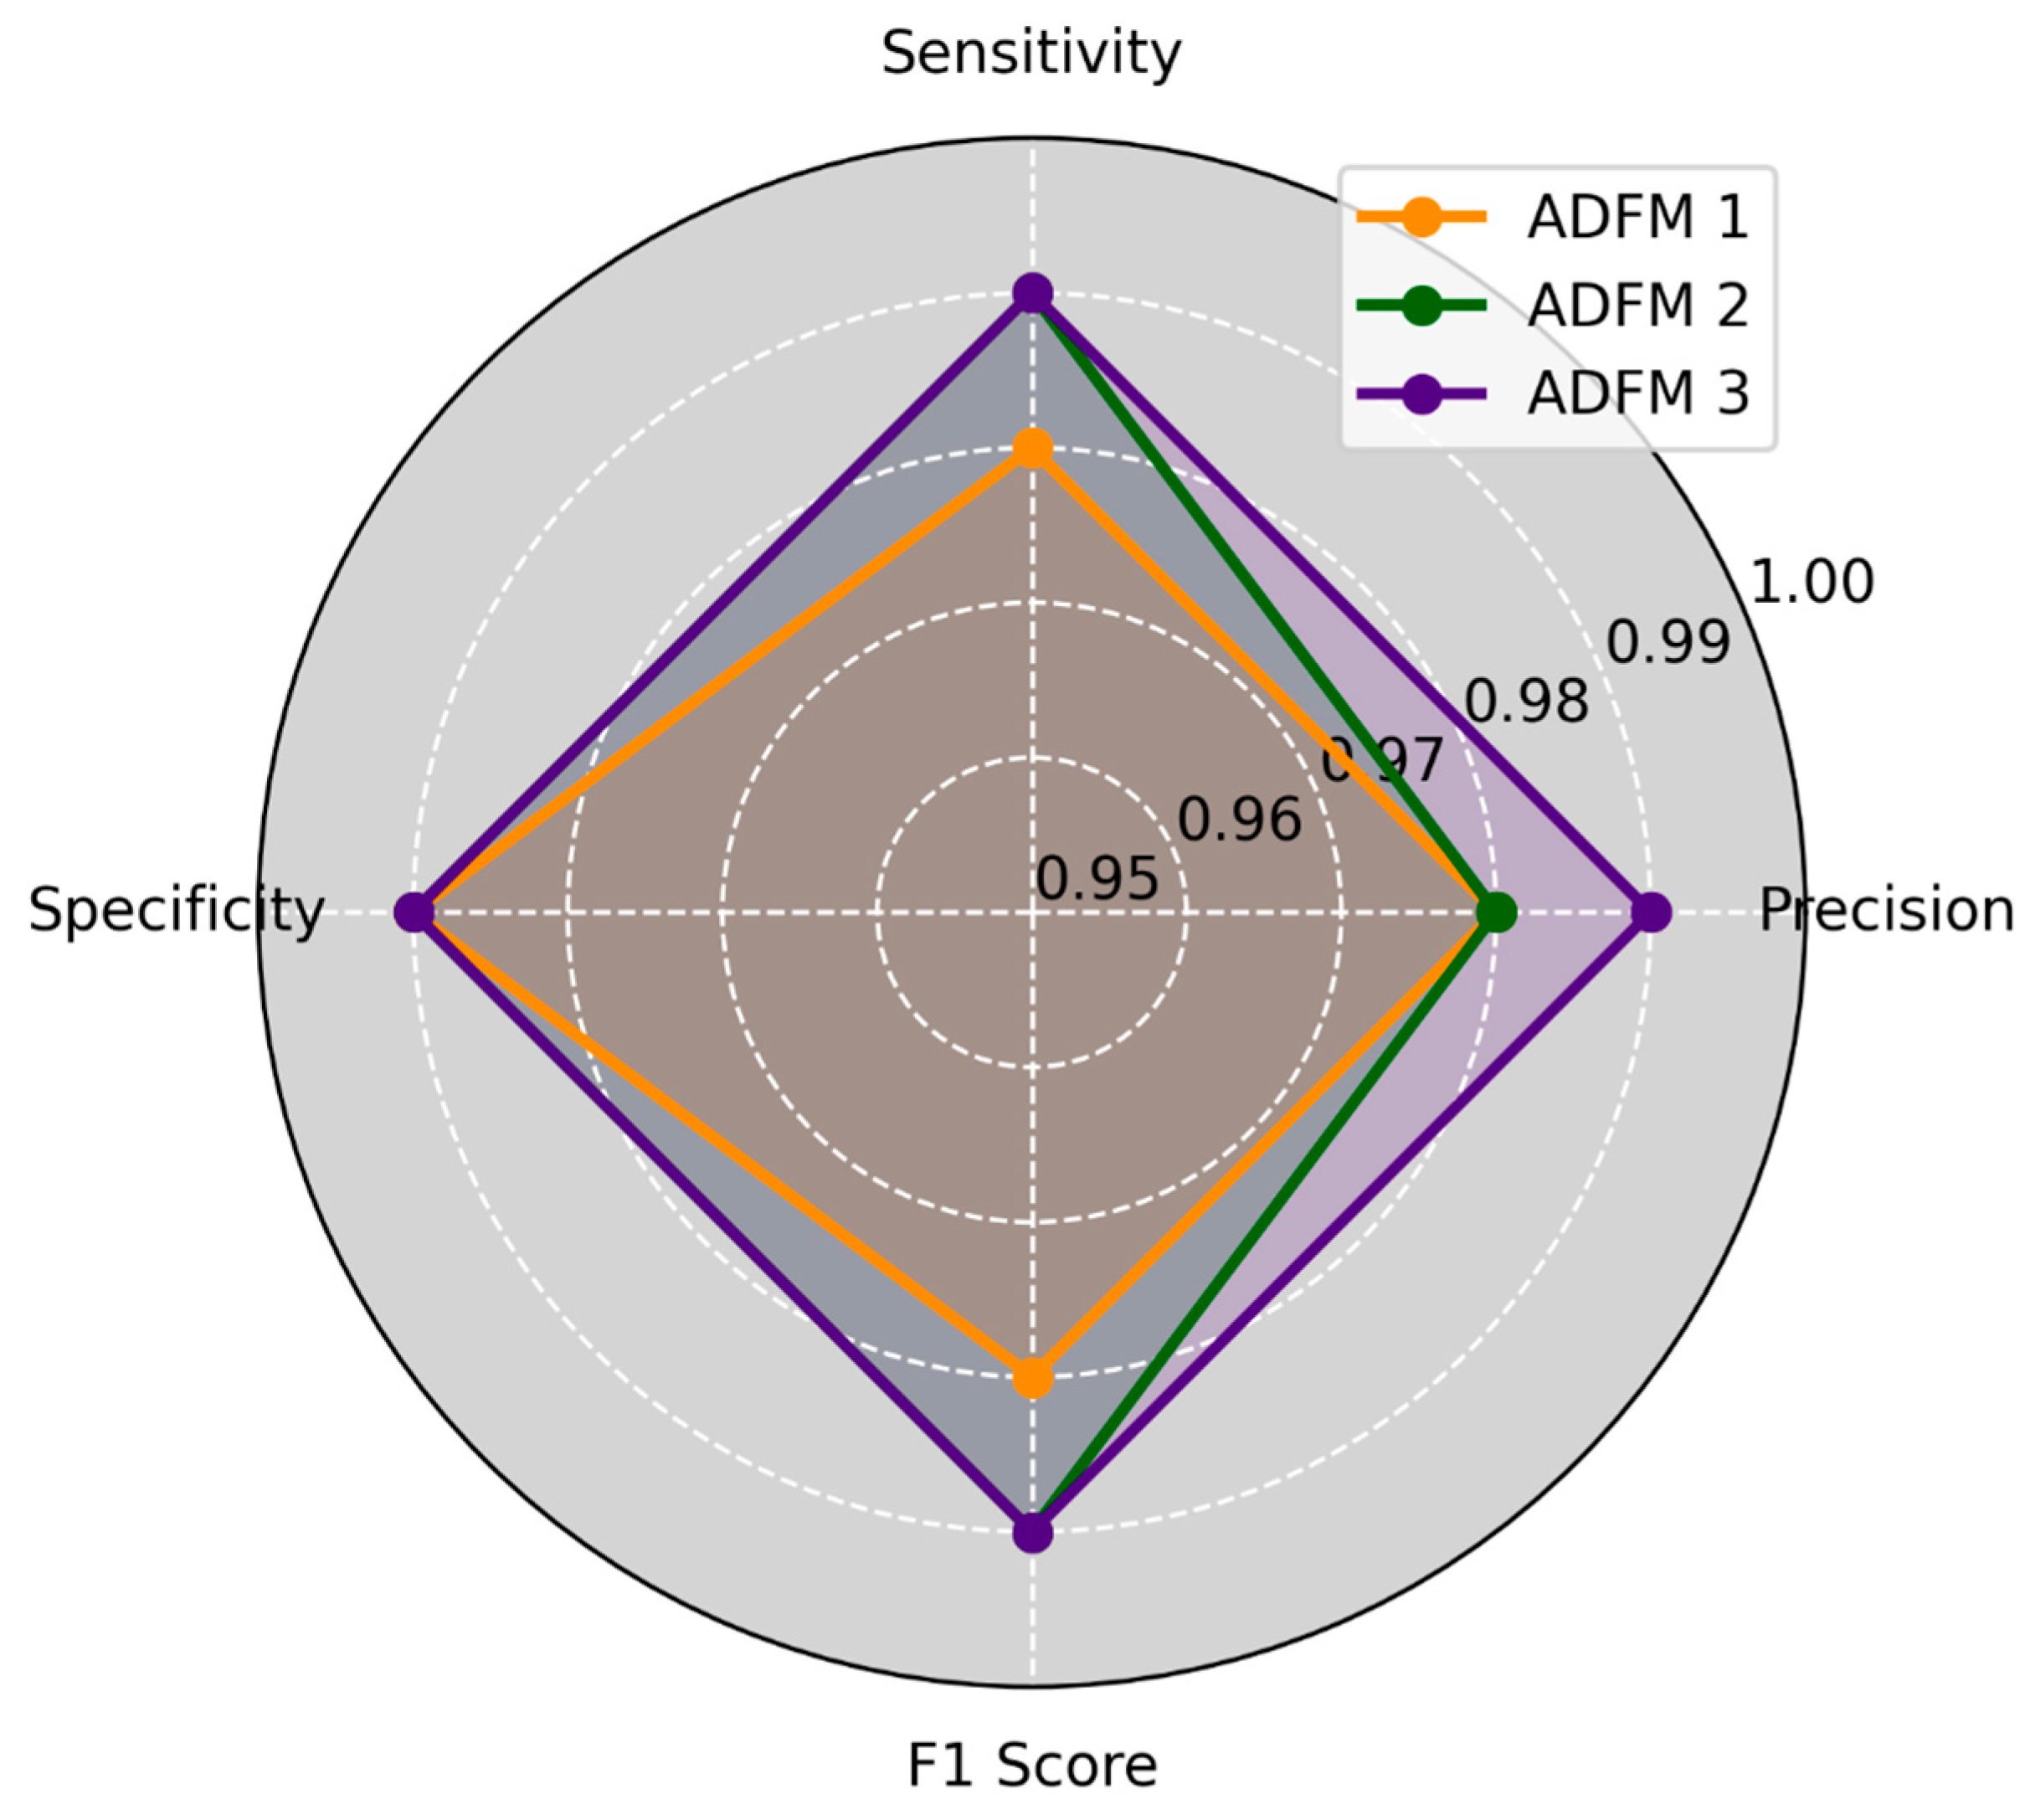

3.2. Performance Comparison of Baseline Versus ADFMs

3.3. Proposed Model Performance Metrics by Class Across Six Datasets

3.4. Experimental Results

3.5. K-Fold Cross-Validation for ADFMs